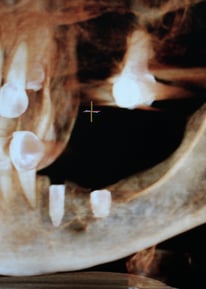

Comprometidos con la excelencia, enseñamos técnicas innovadoras en implantología y cirugía oral, formando a los futuros referentes del sector. Ofrecemos diferentes posibilidades de formación: online y presencial, damos formación para aquellos doctores que quieren aprender a hacer cirugía guiada sin fabricarse sus propias guias, y por otro lado damos formación para los doctores que quieren aprender las dos cosas, realizar cirugía guiada, y fabricarse sus propias guías quirúrgicas.

Capacitación en técnicas de cirugía guiada para cirujanos.